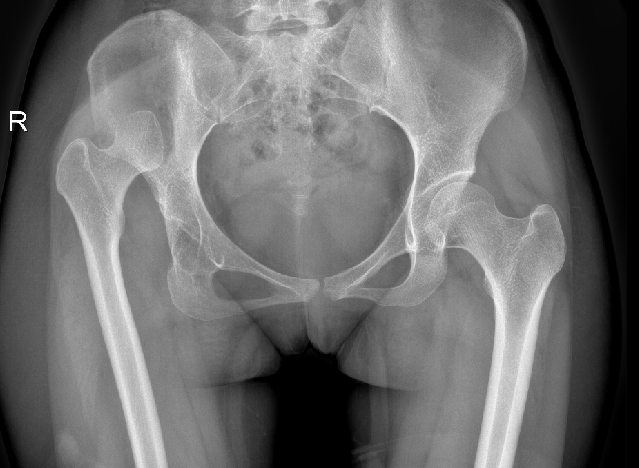

经过详细检查,医生发现丹丹的右侧髋臼已严重磨损,右下肢比左侧缩短了2.5cm,髋关节也出现了脱位,已经具备明确的手术指征,唯有通过手术,才能彻底解决她的困扰。

(X片显示右髋关节已明显存在脱位情况)